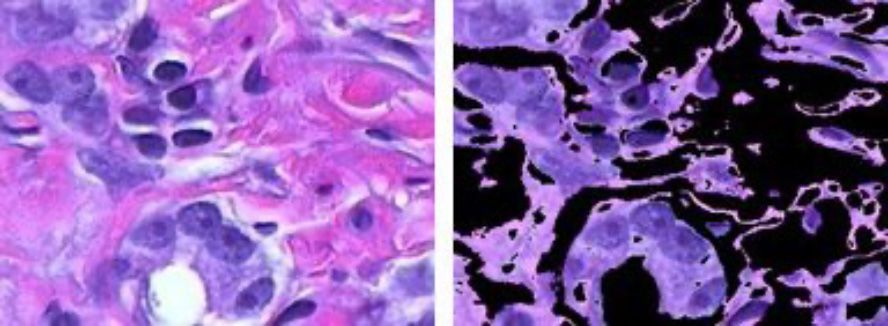

Color-based image segmentation using k-means clustering.